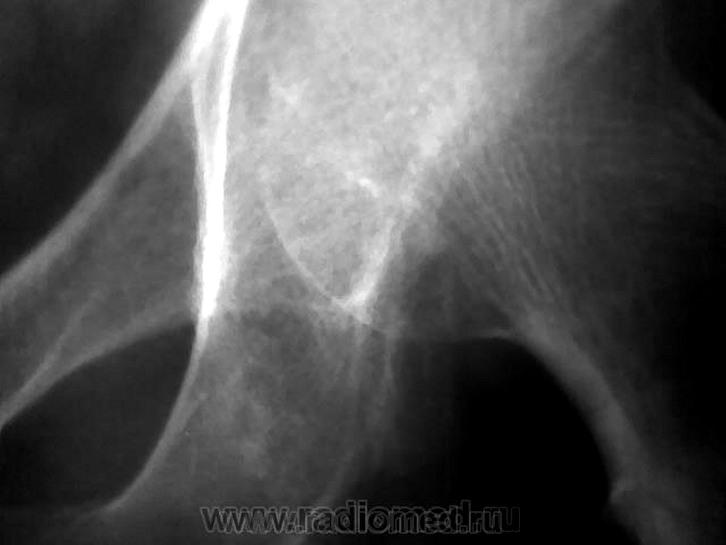

Неоднородность структуры седалищной кости за счет нечетких просветлений. В первую очередь, заподозрила бы мтс. На дополнительных изображениях вроде мягкотканный компонент по нижней границе суставной капсулы. Хотелось бы сравнительное изображение обоих суставов да и верхней/3 бедер

Не исключая остеолитический метастаз все же складывается мнение о суммации теней мягкотканного компонента, вот почему и было высказано мнение о пахово-мошоночной грыже.

Трудности в оценке рентгенограммы тазобедренного сустава понятны: он не поместился на снимке. Большие проблемы с плёнкой??

Может пусть хирург пахово мошоночную грыжу поищет?.....

Остеолитический МТС?